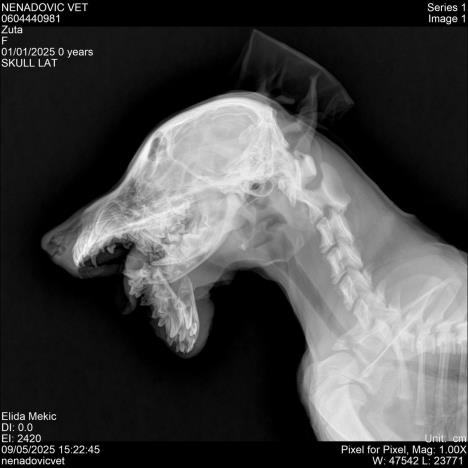

- Slomljena mu je vilica. Nije udareno kolima, nije doživelo nesreću — ovo je delo čoveka. Svesno. Namerno. Bezdušno. Zar živimo među onima koji su sposobni da ovako nešto urade? Ovo nije samo napad na jedno bespomoćno biće, ovo je opomena — jer ko je sposoban da ovako povredi štene, sposoban je da povredi i čoveka, kaže za RINU Anes Muzurović.